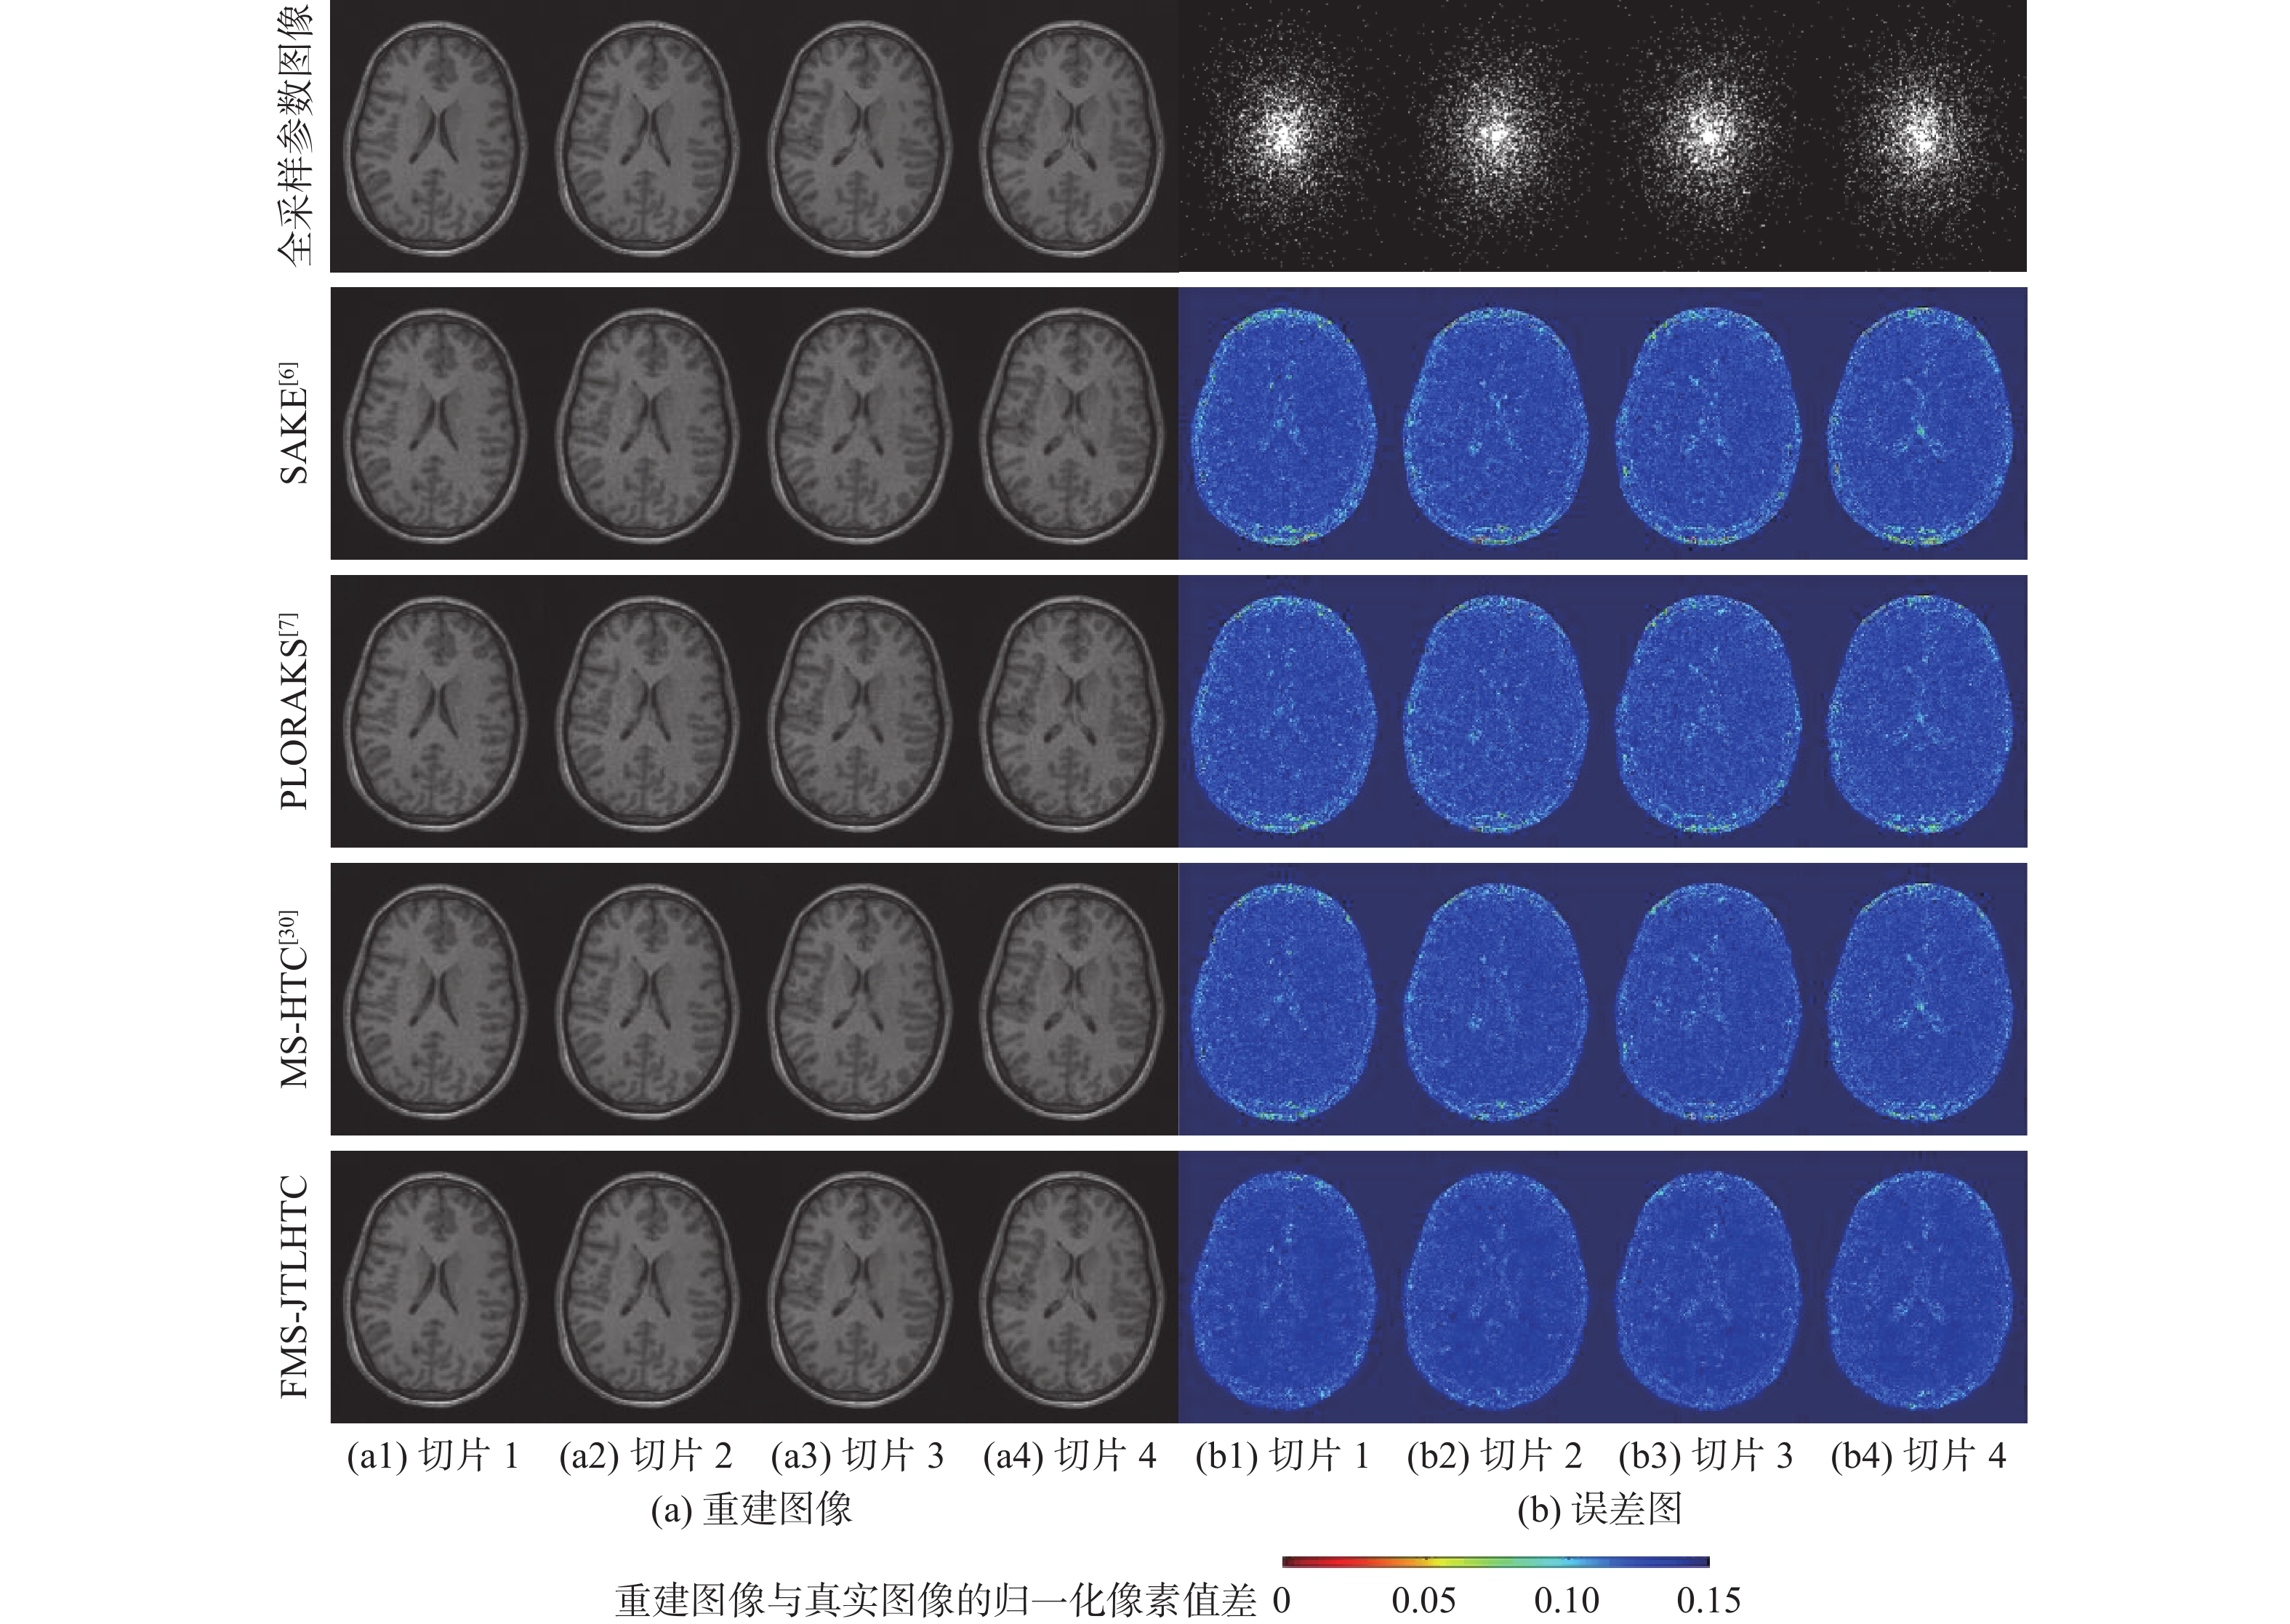

A low-dose CT deep unfolding network based on a sparse transform priors constrain

WANG Yue, ZHANG Xiong, SHANGGUAN Hong, CUI Xueying, ZHANG Pengcheng, GUI Zhiguo

2026, 52(4): 1199-1210. doi: 10.13700/j.bh.1001-5965.2024.0049

Abstract:

Deep iterative unfolding networks have garnered a lot of attention lately because of their great learning capabilities and good interpretability. The regularization terms in existing CT image reconstruction methods mostly focus on information within a specific domain, leading to issues such as edge blurring and information loss in the reconstructed results. Therefore, a sparse transform prior constrain based deep unfolding network is proposed for sparse-view CT reconstruction. Two regularization terms with complementary information—transform-domain sparse regularization and pixel-domain consistency regularization—are created in consideration of the important roles that both pixel-domain and transform-domain information play in picture reconstruction. Based on these, the objective function for sparse-view CT reconstruction is redesigned. Furthermore, a new deep unfolding network for iterative reconstruction of low-dose CT is created by mapping a set of constraint relationships established from an iterative optimization solution for the constructed objective function. Experimental results demonstrate that the algorithm presented in this paper achieves a great improvement on average peak signal to noise ratio (PSNR) and visual information fidelity (VIF) compared to the classical FISTA algorithms.